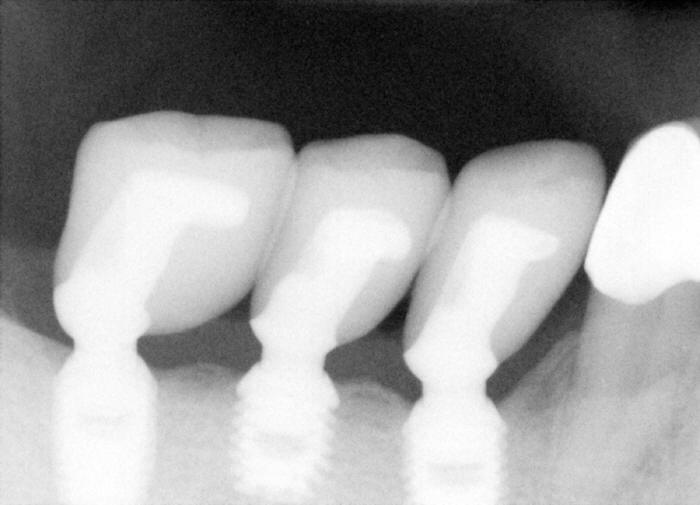

This PA is taken 28 months after crown placement, back to original article